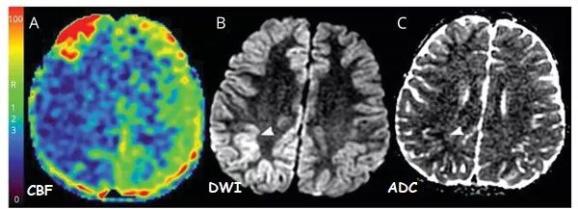

明显可见,灌注有助于癫痫类卒中的早期鉴别(图4)。

图4:2例通过灌注鉴别的类卒中患者(源自曹勇军教授讲课PPT)

6岁男孩,偏头痛家族史。严重、单侧、搏动性头痛3d,出现急性左侧无力和左侧偏盲。症状发作后3h MRI显示整个右半球灌注不足,DWI显示局灶性高信号,ADC低信号,主要累及右顶叶,提示缺血。头痛停止后,出院时无神经功能缺损。

图6:偏瘫型偏头痛 (源自曹勇军教授讲课PPT)